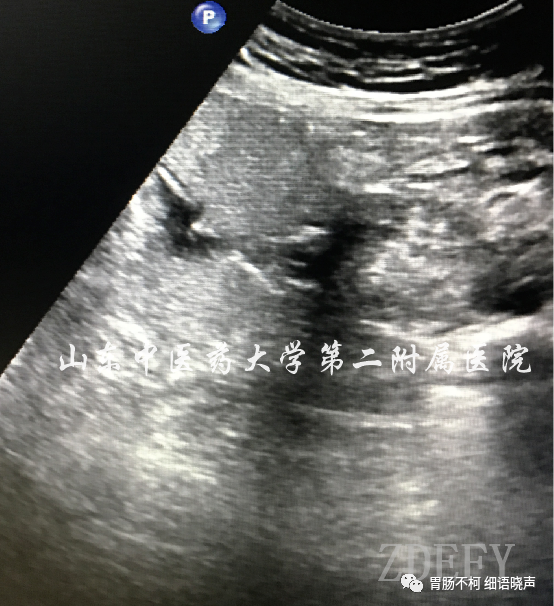

“土堆挖坑征”是恶性溃疡的征象。恶性溃疡发生的病理基础是肿瘤因生长过快,其中央肿瘤组织因血液供应不足导致缺血坏死,坏死组织脱落形成溃疡。所以,是宛若平地的胃壁新生物在先(“土堆”形成),坏死组织脱落溃疡形成在后(挖坑),故为“土堆挖坑征”。溃疡底部因坏死组织脱落所致不平整。典型病例如下: